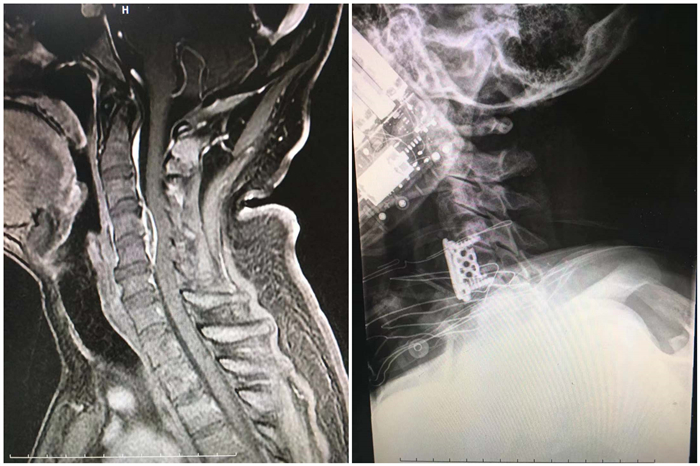

患者邓某,45岁,自幼双目失明,牛羊接触史多年,半月前无明显诱因出现颈部疼痛,期间在当地给予针灸理疗,症状迅速加重,2天前出现双上肢无力,双下肢活动不能(全瘫:肌力0级),排尿困难。经我院神经外科就诊转入我院骨三科,杜鹏主治医师介绍说,“该患者的核磁共振结果显示,位于颈4-5椎体后方占位,脊髓明显受压,严重影响患者的行动能力。”进一步完善检查后诊断为布氏杆菌性脊柱炎伴颈髓脓肿形成,面对患者对更高生活质量的渴求和对医生的信任,骨三科全体医师讨论决定为患者实施手术。手术由兰荫梧主任主刀,经过充分的术前准备,手术如期进行。手术历时3个小时,术中患者生命体征平稳,手术顺利进行,术后患者病情日渐恢复,出院时由家属搀扶下跳了一段“流畅”的交际舞,出院后长期随访,目前患者颈髓神经功能恢复正常,四肢活动自如,患者满意度很高,美好的生活在继续。